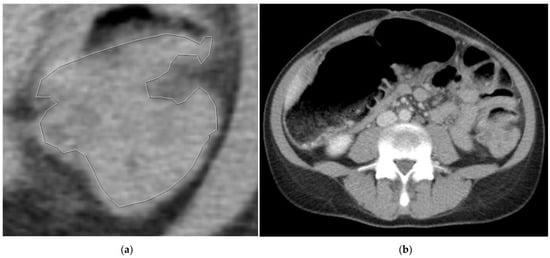

2.3. Segmentation